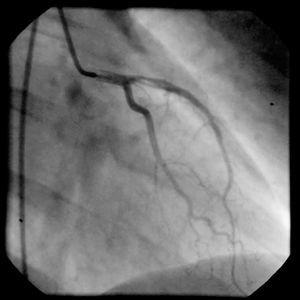

Ante la contraindicación relativa de la fibrinólisis en este contexto, se decidió la realización de un cateterismo cardíaco. En éste se objetivó arteria descendente anterior con una estenosis proximal inferior al 30%, con contenido trombótico y un flujo TIMI III (trombolysis in myocardial infarction). No se observaron lesiones en otros vasos, y la fracción de eyección ventricular fue normal. Asimismo, se evidenció una hipocinesia anterior (fig. 2).

Figura 2. Coronariografía en la que se observa la arteria descendente anterior proximal con contenido trombótico pero con buen flujo distal.

Dada la respuesta positiva eléctrica y clínica al tratamiento médico y los hallazgos de la coronariografía, se decidió no intervenir en un primer momento y observar la evolución.